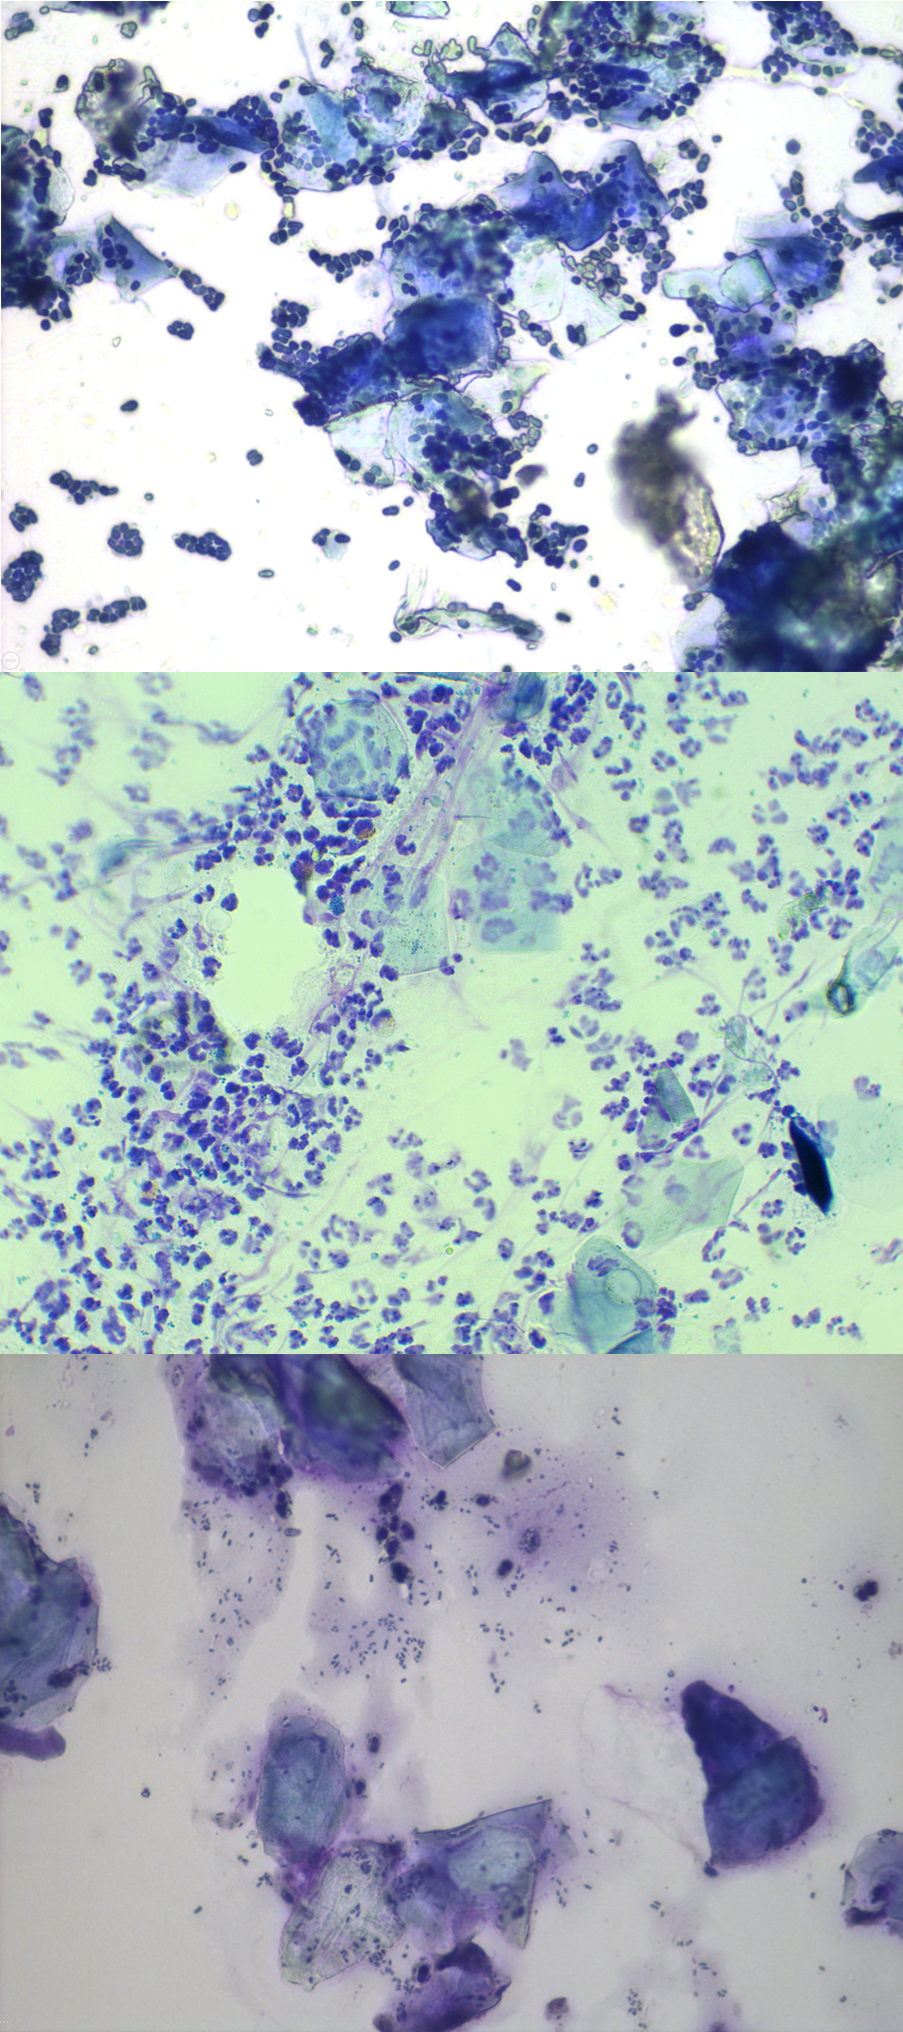

Ces images illustrent différentes étapes et différentes formes d’otite.

Images (CWalker, ThePhotoVet)

L’étape suivante consiste à prélever un échantillon d’éventuels débris présents dans l’oreille de votre chien afin de l’examiner au microscope.

Cet examen, connu sous le nom de cytologie, est un test simple et rapide, que votre vétérinaire peut directement réaliser au cabinet et qui l’aidera à détecter d’éventuels signes de prolifération de bactéries ou de levures.

Le vétérinaire utilise une brosse cytologique et un coton-tige, ou éventuellement un doigt ganté, pour prélever un échantillon dans l’oreille de votre chien et le déposer sur une lame de verre. L’échantillon est ensuite séché avec une solution de coloration pour permettre au vétérinaire d’examiner ce qu’il se trame dans l’oreille de votre chien au niveau microscopique. L’objectif de l’examen est de voir s’il y a une prolifération de bactéries ou de levures et de rechercher la présence de cellules inflammatoires qui sont invisibles à l’œil nu.

La cytologie permet à votre vétérinaire non seulement de choisir le traitement approprié, mais aussi de surveiller l’efficacité du traitement lors des visites de suivi et de l’adapter, si nécessaire. Sans oublier qu’elle l’aide à élaborer un plan à long terme pour la prise en charge des problèmes d’oreilles de votre chien.